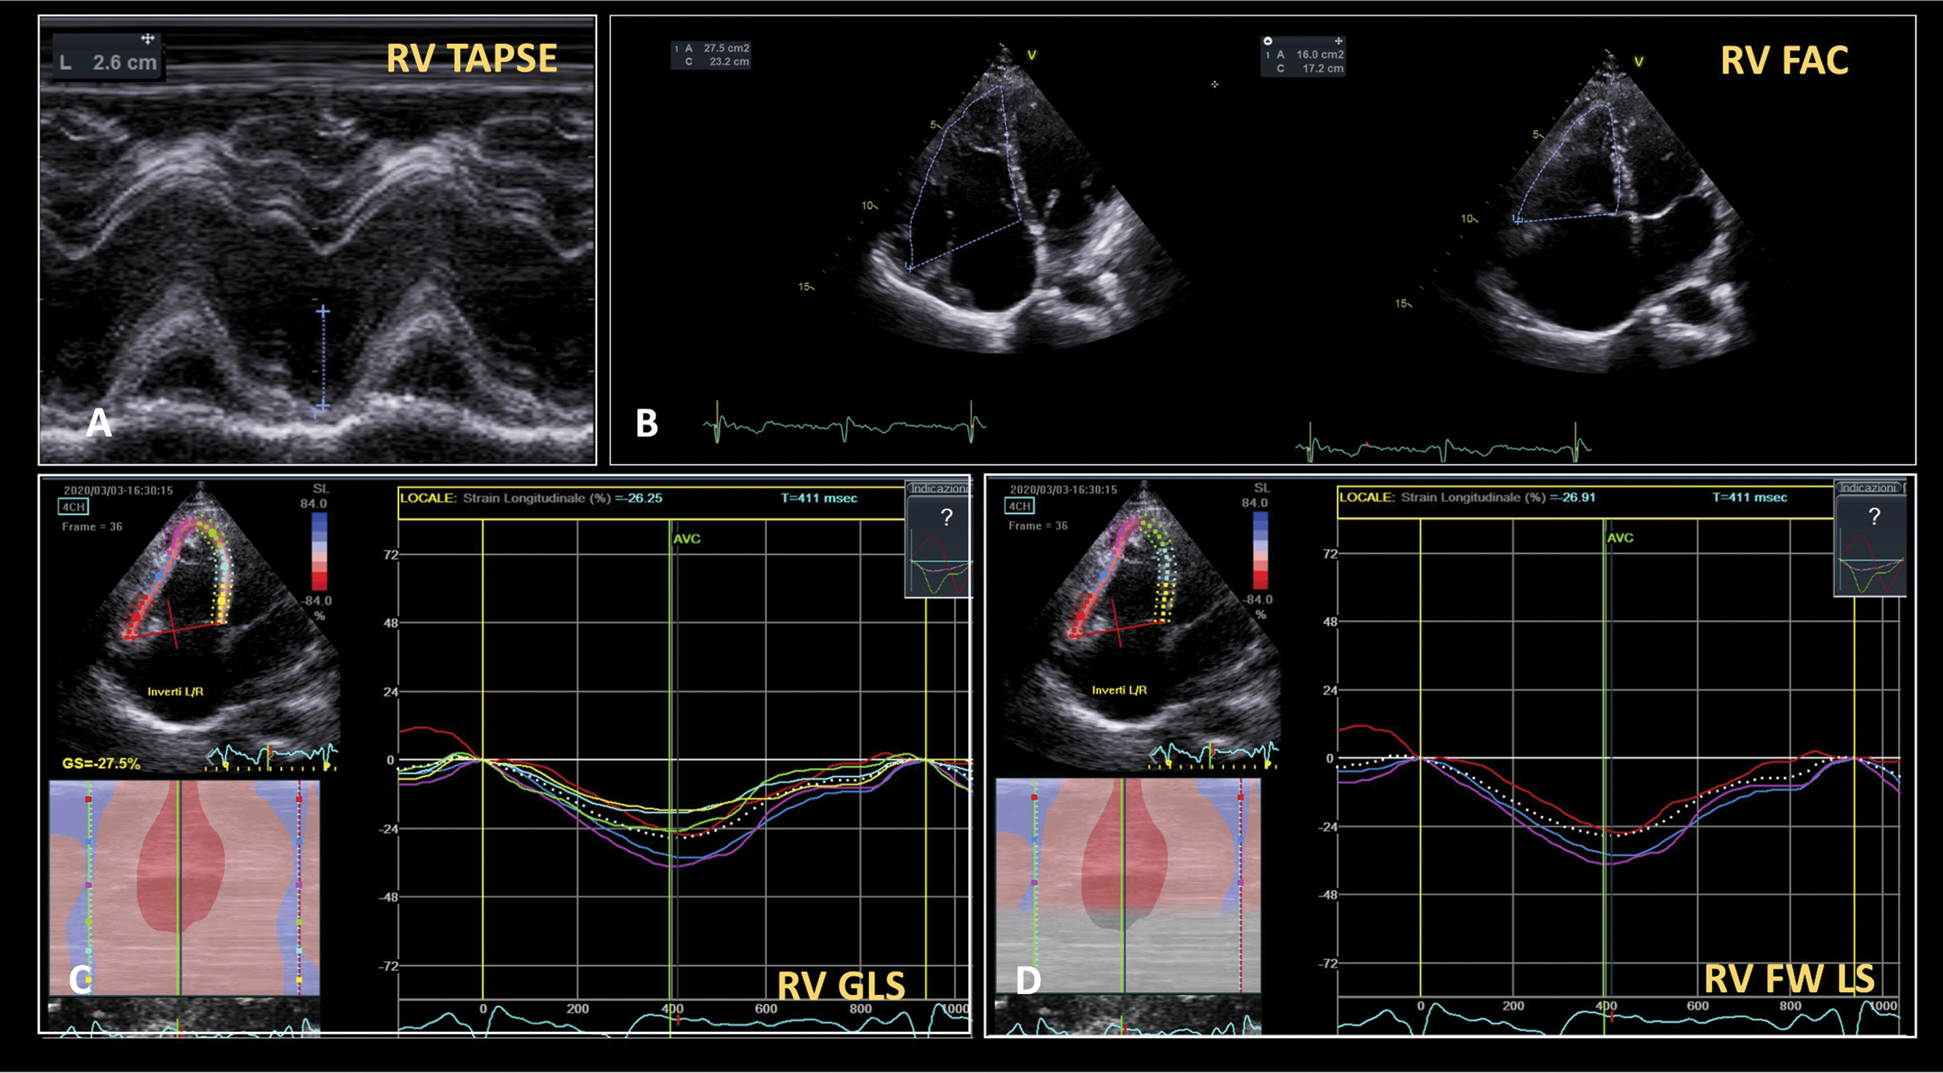

On physical examination she had a 2/6 systolic murmur at the left lower sternal border and no clinical signs of heart failure. She was afebrile and her blood pressure was 105/70 mmHg. The TTE confirmed the RV and atrial enlargement (RV Basal 50 mm; RV Mid 40 mm; Right Ventricular Outflow Tract (RVOT) Parasternal short axis proximal 34 mm; RVOT Parasternal Long Axis 32 mm; Right Atrial Volume index, RAVi, 45 ml/m2), with normal RV function (Tricuspid annular plane systolic excursion, TAPSE, 26 mm; Fractional Area Change, FAC, 41%) (Fig. 1). The Color-Doppler showed turbulent flow along the atrial septum, without overt shunt. A moderate-to-severe TR (Proximal Isovelocity Surface Area, PISA, Radius 7 mm; vena contracta 7 mm; TR Vmax 3.05 m/s) with PAPs = 45 mmHg was also evident. The inferior vena cava (IVC) had normal diameter (15 mm) with normal collapsibility during inspiration. Left ventricle and atrium were normal (LV End Diastolic Diameter, LVEDD, 46 mm; LV End Systolic Diameter, LVESD, 26 mm; Left Atrium Volume index, LAVi, 27 ml/m2; Ejection Fraction (EF) 57% Simpson Biplane; E/A 1.5; average E/e’ 4.5). Right Ventricular Global Longitudinal Strain (GLS–25.1%) and RV Free Wall Longitudinal Strain (RV FWLS–26.9%) were within the normal range (Fig. 1).

Figure 1: Right ventricular function evaluation. RV function evaluation using both TAPSE (Panel A), RV FAC (Panel B) and STE-based RV Global Longitudinal Strain (Panel C) and RV Free Wall Longitudinal Strain (Panel D). All indexes reveal normal RV function. FAC = Fractional Area Change. RV = Right Ventricular. STE = Speckle Tracking Echocardiography. TAPSE = Tricuspid Annular Plane Systolic Excursion